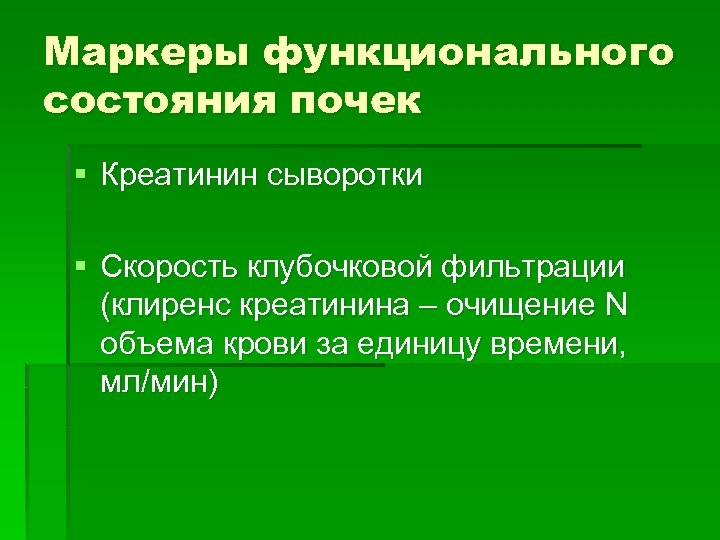

Маркеры функционального состояния почек § Креатинин сыворотки § Скорость клубочковой фильтрации (клиренс креатинина – очищение N объема крови за единицу времени, мл/мин)